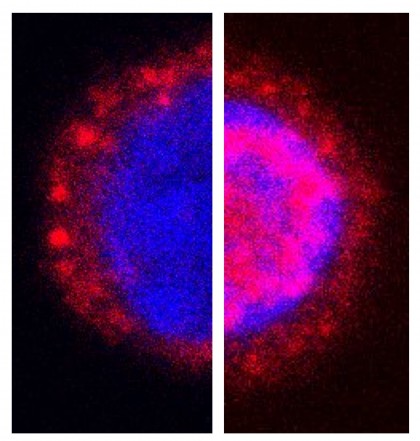

În acest context, Dominique Tandl, cercetător la Departamentul de Biologie de la TU Darmstadt, afirmă că studiul s-a concentrat pe efectele iradierii selective a limfocitelor T cu radiațiile X folosite în cadrul tratamentului tumorilor, astfel evidențiindu-se efectul acestora asupra declanșării cascadei de semnalizare specifică răspunsurilor imunitare ce debutează prin eliberarea de calciu din depozitele intracelulare. Mecanismul care stă la baza acestui fenomen este unul de atingere a unor valori critice a concentrației de calciu din celule, astfel că, prin intermediul unui factor de transcripție citoplasmatic care ajunge în nucleul celular, celula începe producerea unor molecule esențiale sistemului imunitar, printre care se numără și citokinele.

foto: Limfocitele T înainte (stânga) și după (dreapta) tratamentul cu raze X. Picture: Gerhard Thiel